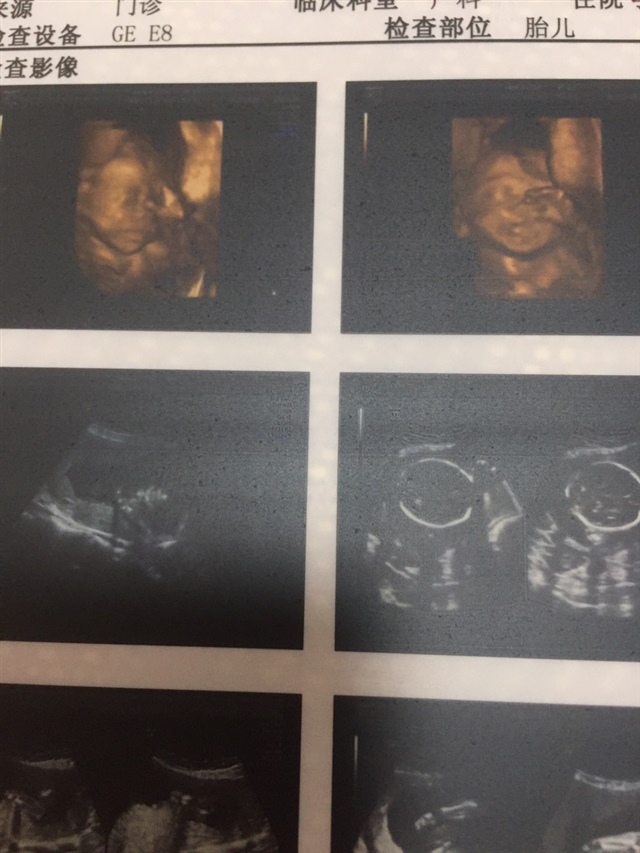

吴海洋

孕22周+1天

真好